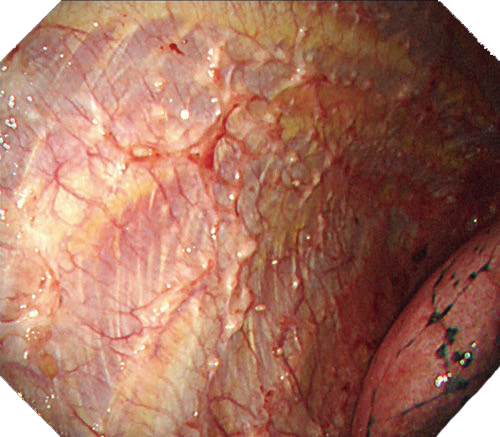

NBI

NBIは粘膜表層の血管走行が強調表示され、高精度な診断をサポートします。新しいスコープではより精細な血管構造の観察に貢献します。